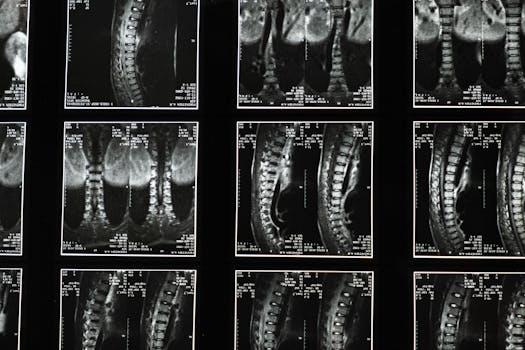

The disc osteophyte complex is a condition that affects the spinal disc and adjacent vertebrae, leading to potential pain and discomfort. This condition can arise… Continue Reading